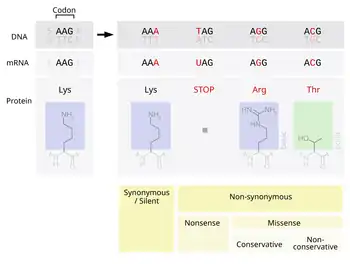

Overlap with Charcot–Marie–Tooth disease type 1A has been found in Gly94fsX222 (c.281_282insG), due to point mutations in PMP22 that occur in a minority of cases of HNPP. The point mutations missense, nonsense and splice-site have each been alluded to in HNPP.[11]